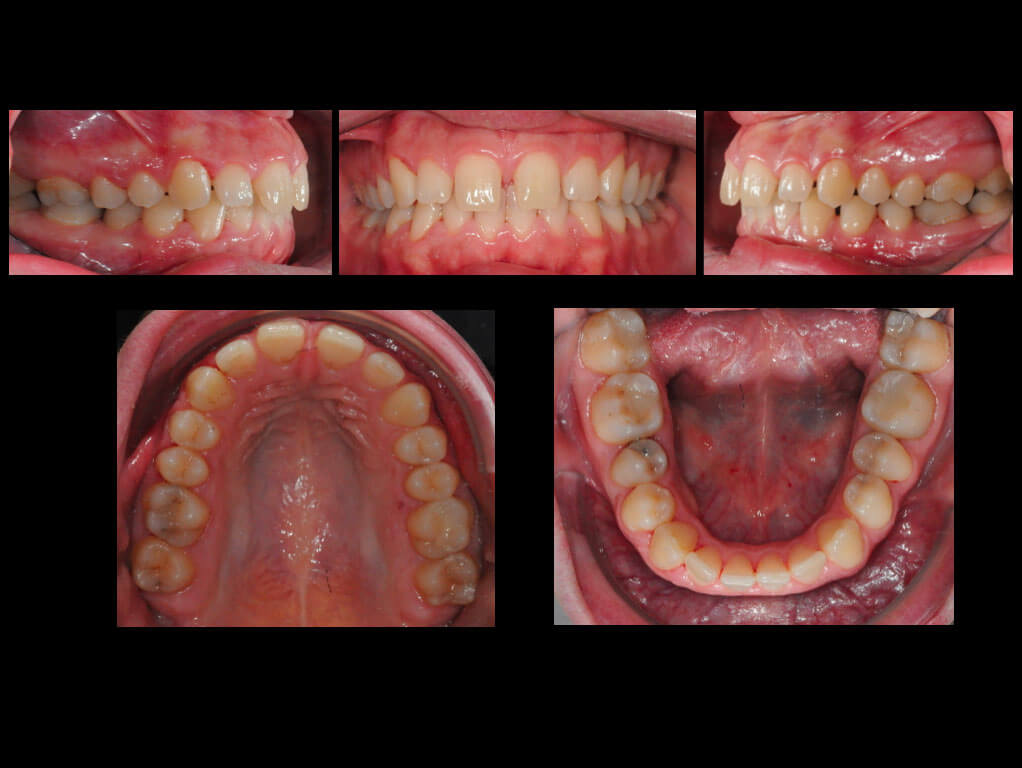

La paziente è stata molto collaborante portando le mascherine secondo le indicazioni, e una volta ottenuto quanto era stato pianificato, il protesista (Prof. S. Catapano) ha eseguito delle preparazioni minimamente invasive per permettere il posizionamento di 4 faccette in composito.

Dopo